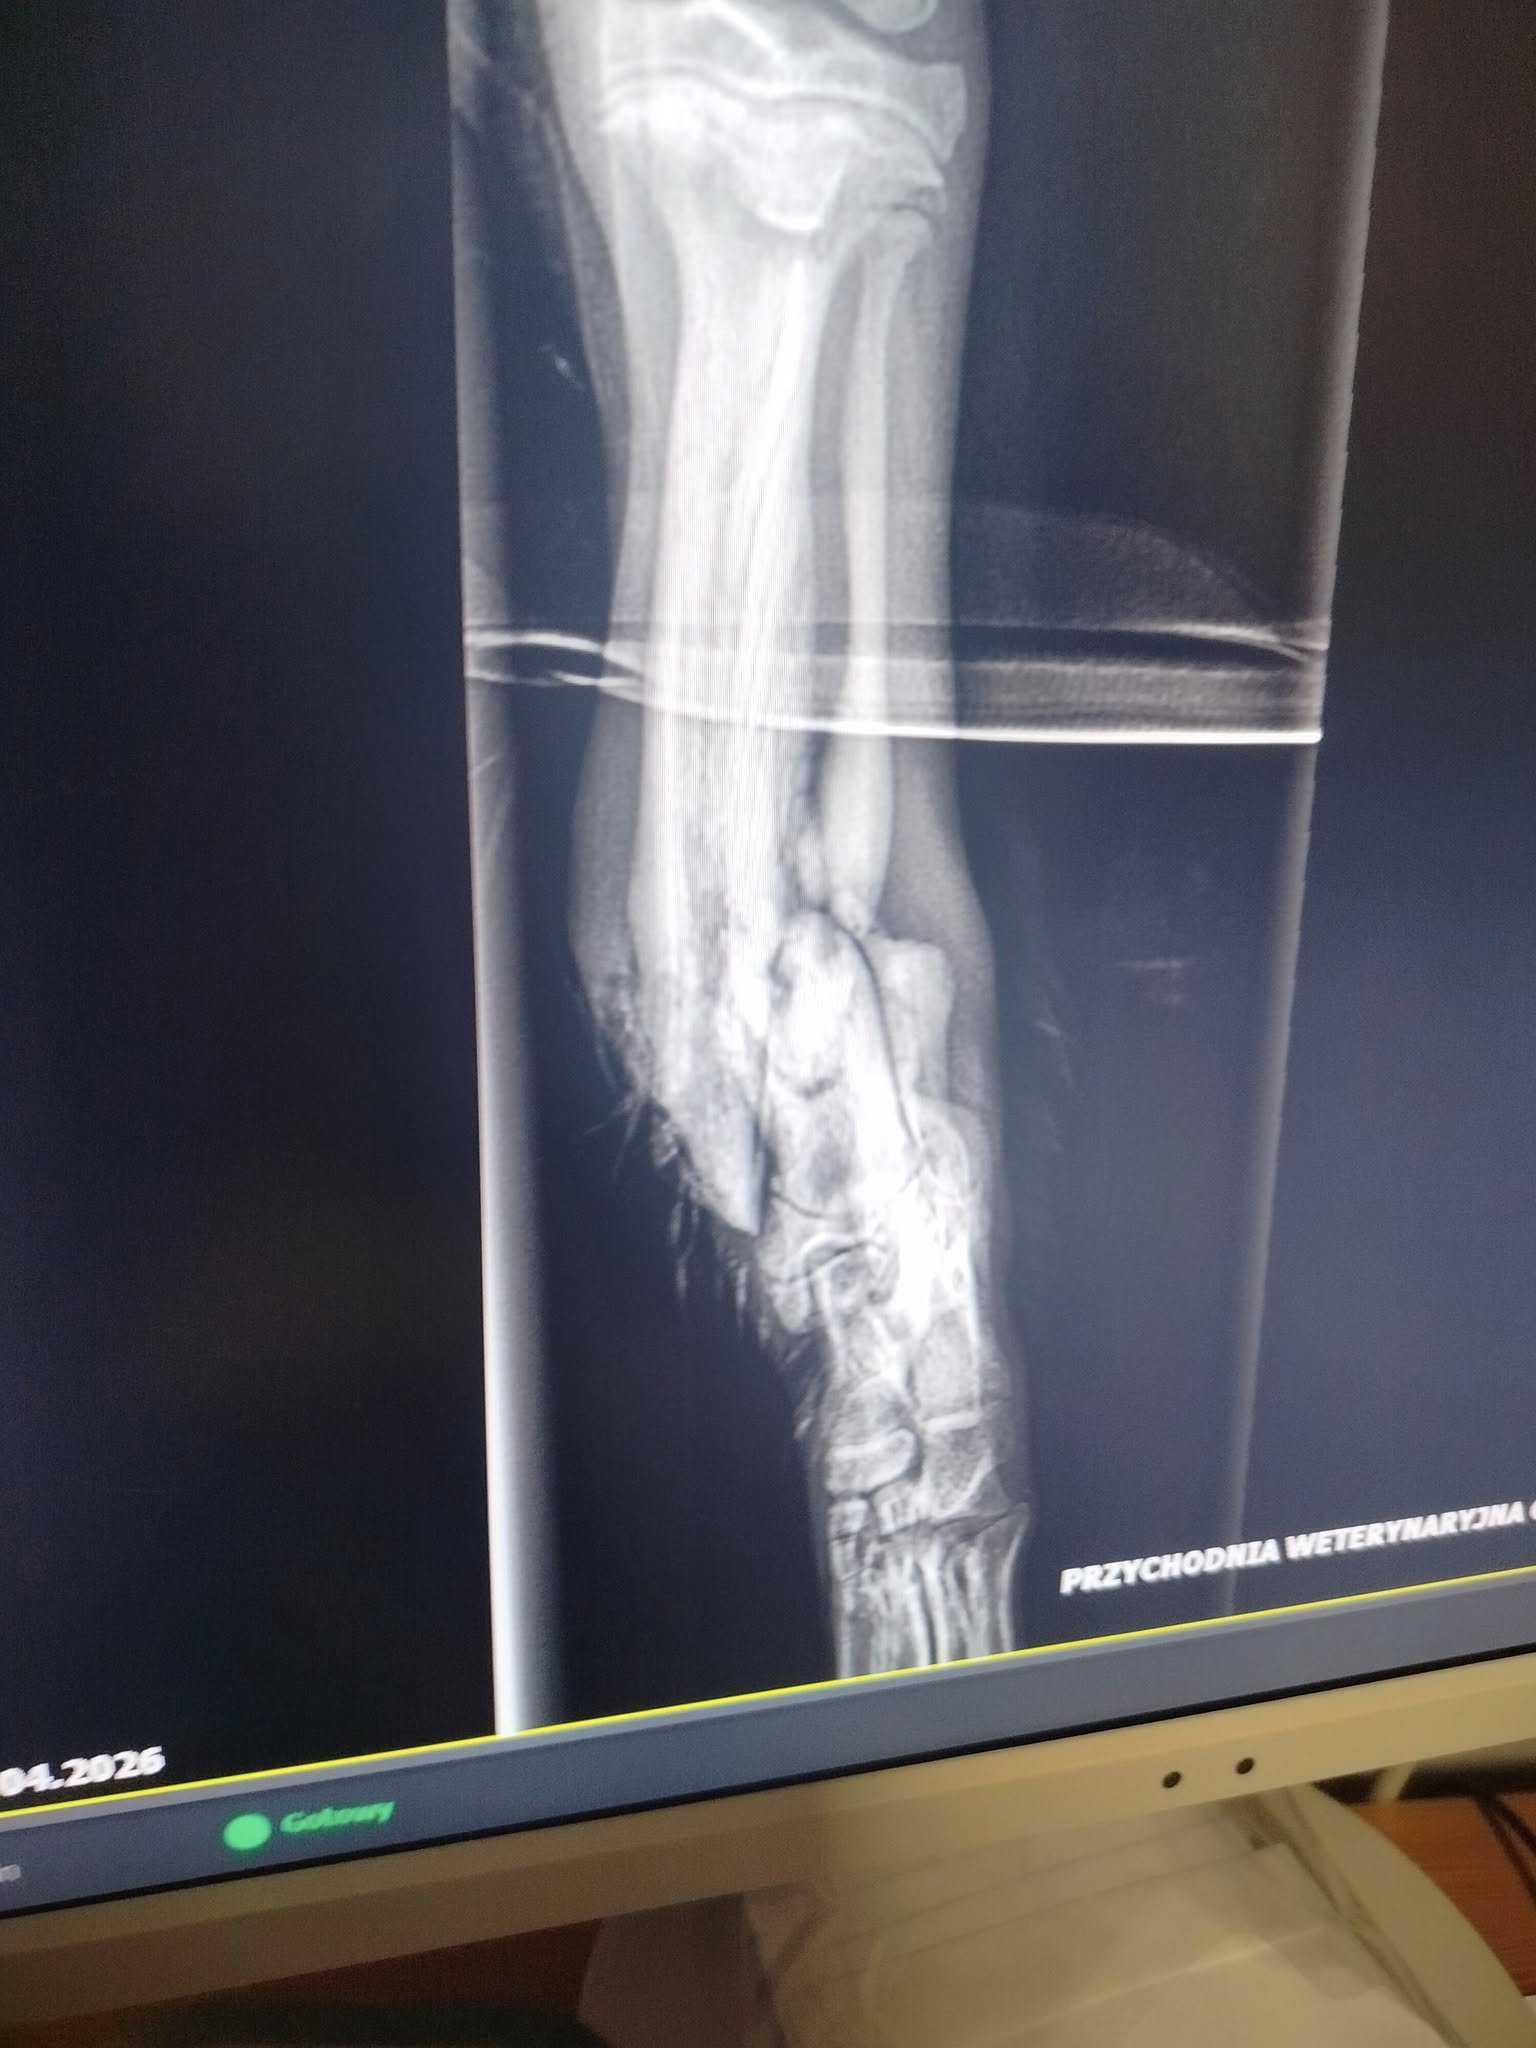

A jego łapa… Otwarte złamanie obu kości.

Dziś lekarze oczyścili ranę, zabezpieczyli kość, dostał silne leki i kroplówki. Ale to dopiero początek drogi.

Ma babeszjozę. Wyniszczenie organizmu. Infekcja jest poważna. Przed nami dni niepewności i decyzji, których nikt nie chce podejmować. Może uda się uratować łapę. Może nie. Ale zrobimy wszystko, żeby uratować jego życie.